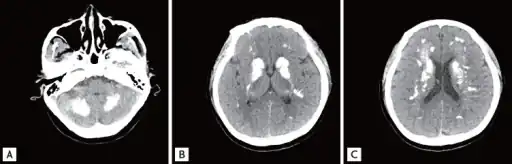

-

a-c)Brain computed tomography shows diffuse symmetric parenchymal calcifications -